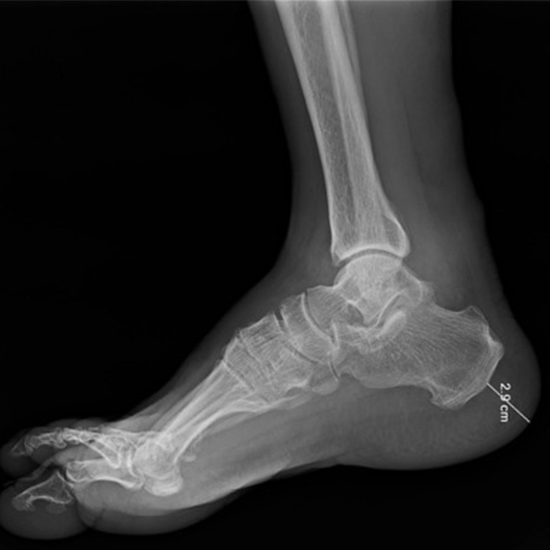

What is an X-ray Left Heel (Calcaneum) Test?

The calcaneus is the name given to the prominent bone located in the rear of the foot. It often breaks when someone falls from a high place or is in a car accident.

Most of the time, calcaneal fractures are found through a physical exam and X-rays. These diagnostic tests also help find out how bad the fractures are.